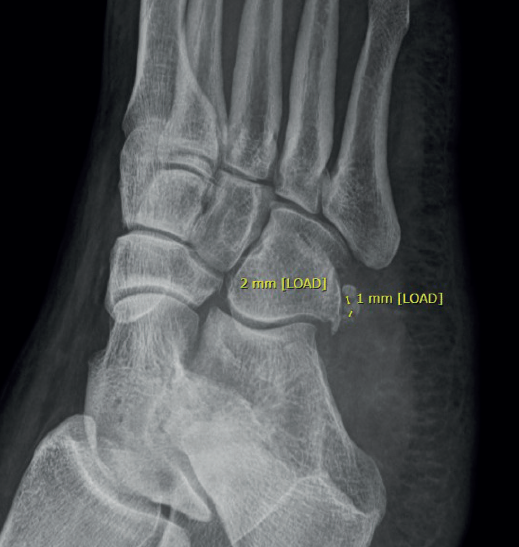

La radiografía y la TC pueden complementarse para demostrar la presencia del OP. Además, pueden determinar si se ha desplazado, fracturado o si presenta separación en casos de OP bipartito(11). Una separación de 2 mm o menos puede observarse en fracturas del OP no desplazadas y en fracturas bipartitas del OP, y separaciones de 6 mm o más de un fragmento del OP sugieren fractura y desgarro asociado del tendón peroneo largo en todo su espesor(12). En este caso, se evidencia separación máxima entre fragmentos de 2 mm (Figura 3). En las fracturas, la RM puede mostrar edema de médula ósea en el OP o al nivel del hueso cuboides, asociado con edema de los tejidos blandos circundantes(13).